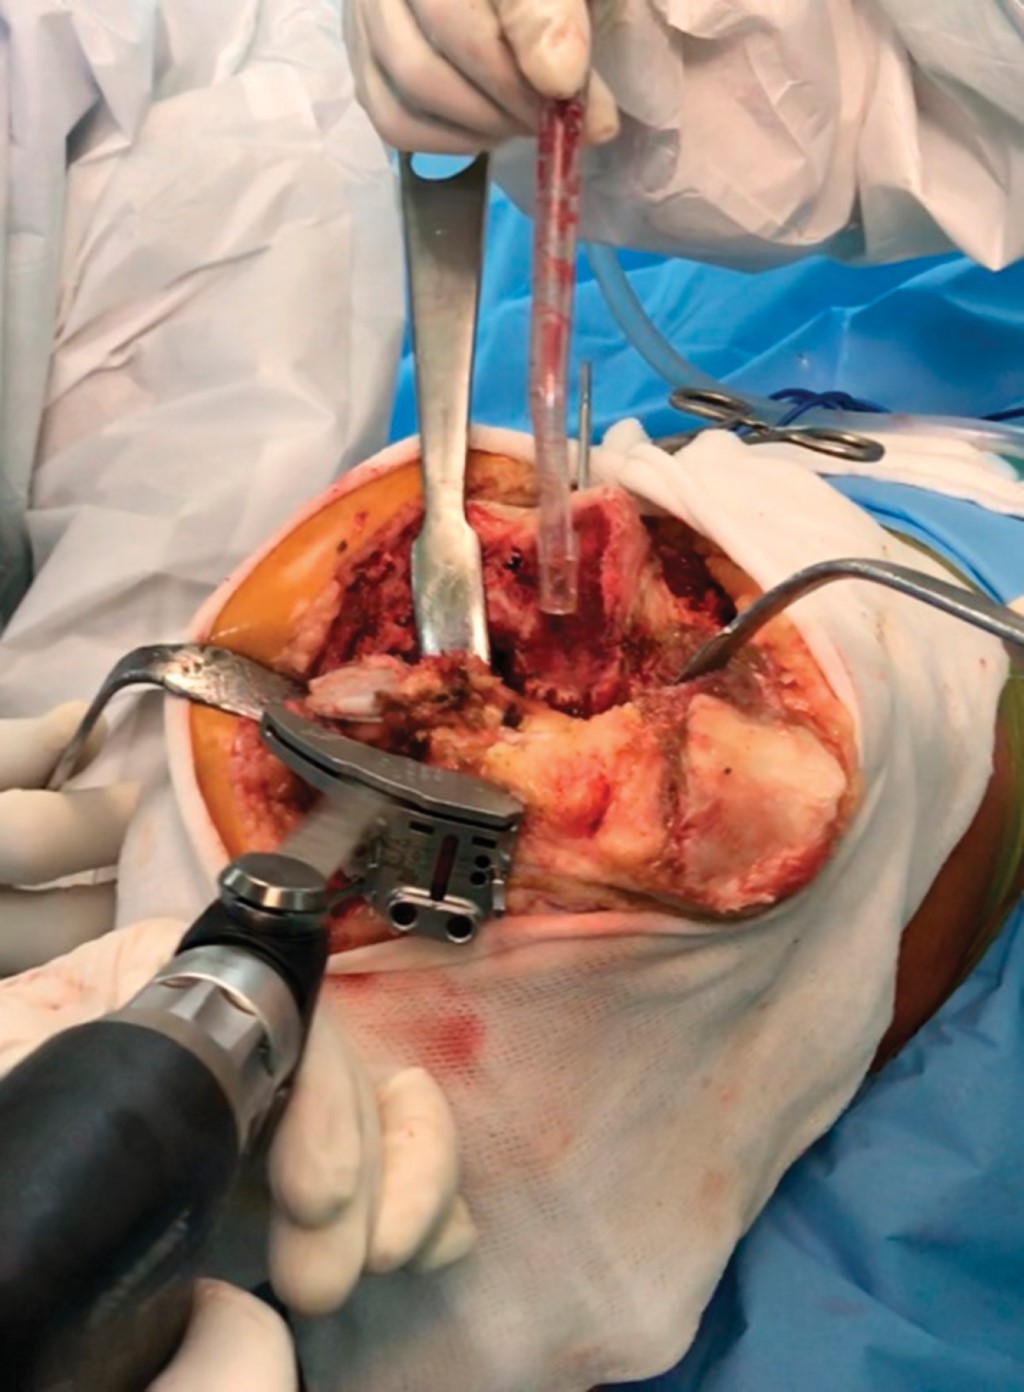

Conversions from failed unicompartmental prostheses to total knee replacement

Figure 1

Figure 2

Figure 3

Figure 4

Figure 5

Figure 6

Figure 7

Figure 8

Figure 9

Figure 10

Figure 11

Figure 12

Figure 13

Figure 14

Figure 15

Figure 16

Figure 17

Figure 18

Figure 19